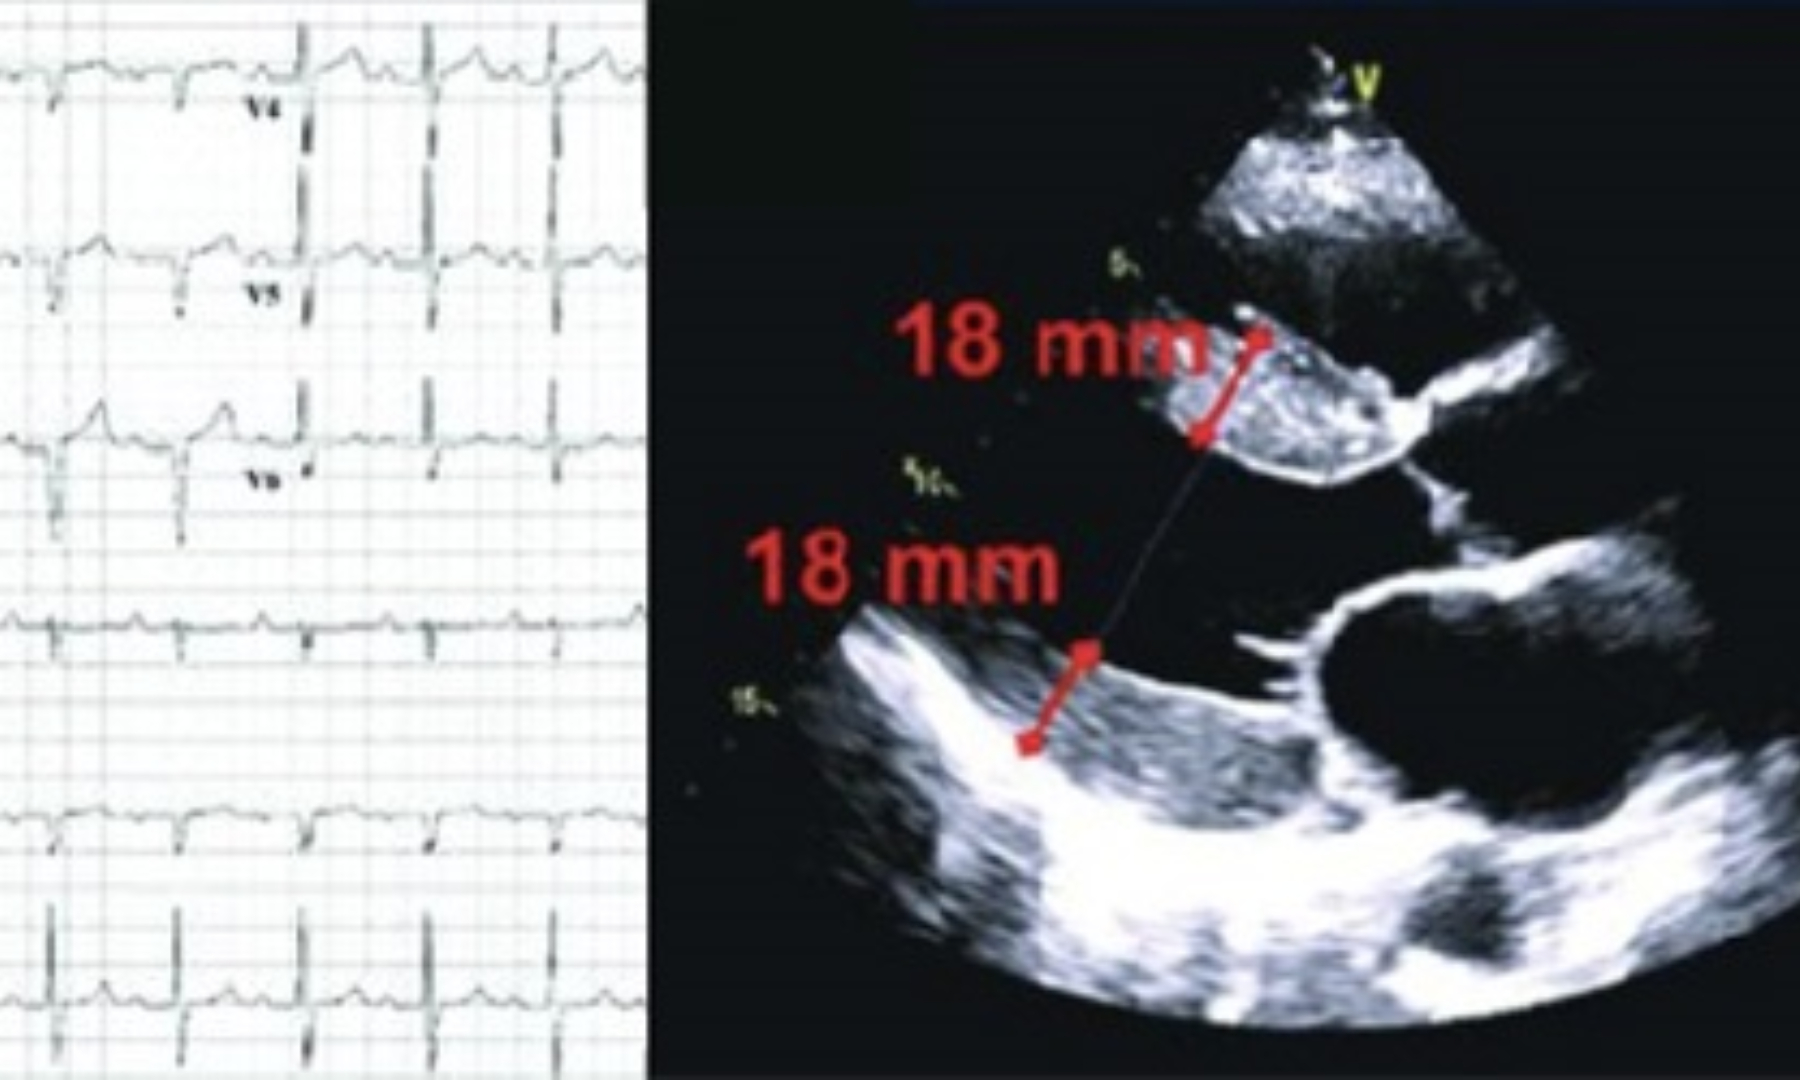

La patologia è determinata, appunto, dall’accumulo di TTR, una proteina prodotta dal fegato necessaria per il trasporto in circolo degli ormoni tiroidei. Per motivi ancora non chiari, questa si frantuma in filamenti singoli, “fibrille”, che si riaggregano cambiando forma e si depositano lentamente negli organi, fra cellula e cellula, con un danno progressivo degli stessi. Nel cuore tale accumulo determina, come manifestazione principale, una Cardiomiopatia che somiglia alla Cardiomiopatia ipertrofica, in quanto le “fibrille” amiloidi si depositano tra i cardiomiociti, ossia le cellule contrattili del cuore, e via via, nel corso degli anni, aumentano lo spessore delle pareti. Possono causare difetti di conduzione dell’impulso elettrico e disfunzione contrattile stessa fino allo scompenso cardiaco, oltre a diverse aritmie (es. Fibrillazione atriale e anche ventricolare). Negli uomini, avere una “Sindrome del Tunnel carpale”, può essere una delle manifestazioni cliniche precoci, e in questo caso la raccomandazione è di fare controlli cardiologici periodici per cogliere l’eventuale successivo interessamento cardiaco.

In uno studio condotto alcuni anni fa in pazienti con diagnosi di Cardiomiopatia Ipertrofica, riferiti alla Unit Cardiomiopatie della AOU Careggi e al Centro Cardiomiopatie dell’Istituto Auxologico, la percentuale dei pazienti che risultarono invece affetti da Amiloidosi cardiaca, di origine genetica e non, aumentava con la loro età, fino a oltre il 20 percento nei pazienti di età superiore a 70 anni. Tuttavia anche nei pazienti più giovani poteva essere identificata: distinguerla è molto importante per la possibilità di usare i nuovi farmaci, la cui efficacia aumenta se l’amiloidosi cardiaca è identificata e trattata precocemente.